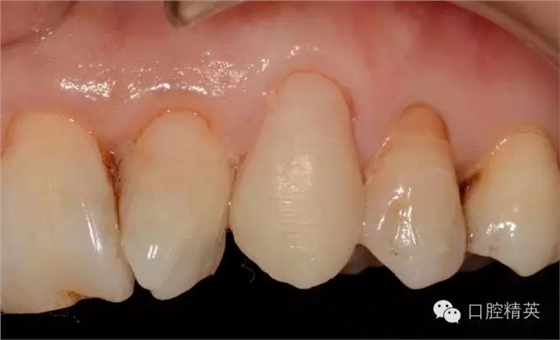

圖5置纖維樁樹脂樁備牙后情況

圖623代臨時(shí)冠口內(nèi)照

圖723備牙后模型照